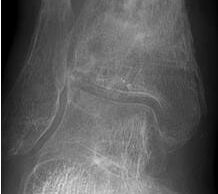

• Revision einer gescheiterten Fusion des OSG/ USG (Abbildung 3, Abbildung 4).